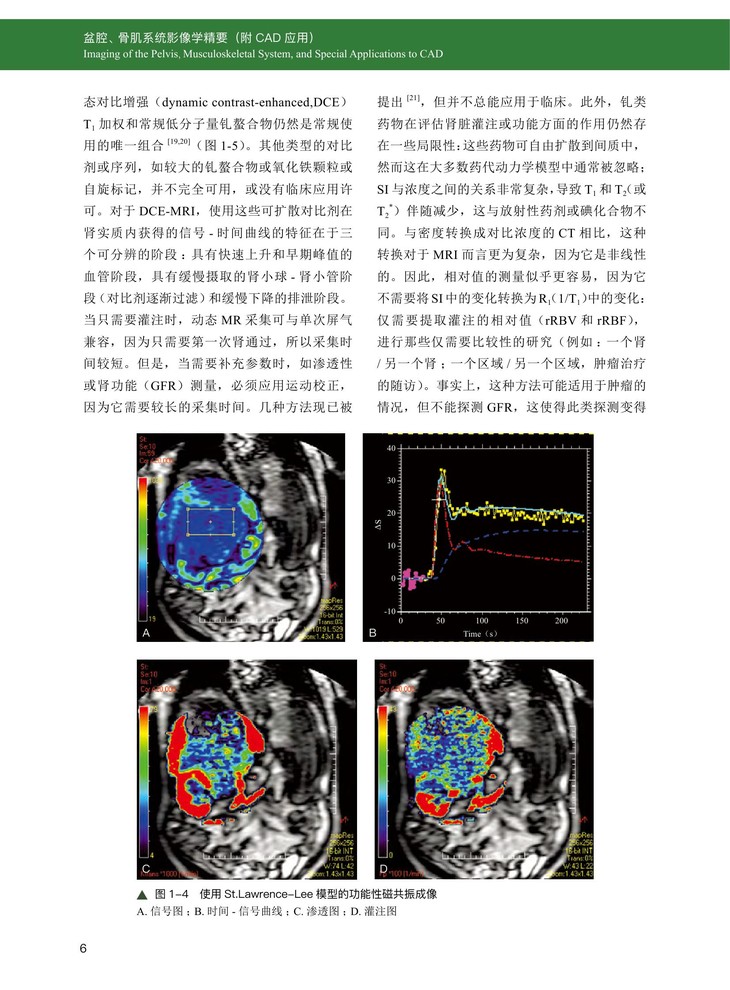

一、肾脏及输尿管 MRI 成像的具体技术规范